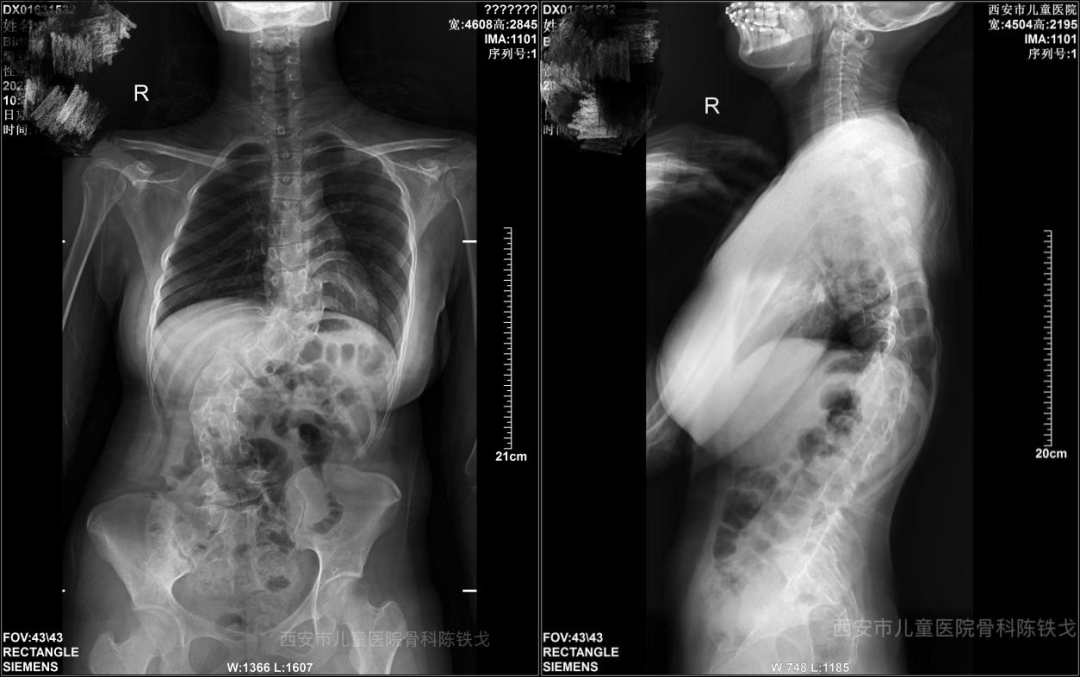

“这是一块难啃的硬骨头。”接诊后,我院骨科团队迅速为患儿进行了全面的影像学评估。结果显示,患儿的脊柱不仅存在复杂的先天性椎体畸形,且侧凸和后凸角度极大,属于重度的僵硬性畸形。

在充分的术前规划和3D打印技术的精准模拟下,由我院骨科领衔的手术团队迎难而上。手术室内,无影灯下,专家们屏气凝神,在神经电生理监测的实时护航下,以毫米级的精度进行对胸段和腰段重度僵硬型畸形椎管减压、截骨松解、置钉矫形,术中电生理监测未见明显异常,术后患儿双下肢感觉、运动良好。

经过7小时的精细操作,手术顺利完成。当术后复查的X光片,整个医疗团队都为之振奋:原本严重扭曲的脊柱被矫正到了近乎生理状态的角度,矫形度数远超预期,堪称“惊艳”。 不仅躯干恢复了平衡,身高也有了增加,被压迫的胸腔容积得到了有效释放。术后,在护理团队的精心照料下,患儿恢复顺利,久违的笑容终于回到了这个少年的脸上。